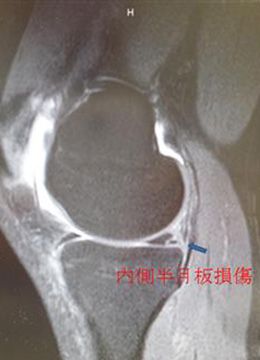

通常自然治癒せず、永続的に膝の不安定性と不安感が残るため、一般的にスポーツ復帰を目標とした場合、手術以外の保存療法は無効とされています。そのまま放置した場合、膝周囲の筋力低下を伴って、頻回の“膝崩れ”によって関節内の半月・軟骨損傷が多発し、近い将来、変形性膝関節症(関節軟骨がすり減って痛む高齢者に多い疾患)となる恐れがあります。

自分の組織を用いて再建する(自家腱移植)のがベストな方法とされています。当院で行っている膝屈筋腱(ハムストリングス)を用いた関節鏡視下膝前十字靱帯再建術は、切開は最小限で大きな合併症がなく、術後の成績も安定しているため、有効な治療方法として確立されています。 手術は膝関節を構成する大腿骨と脛骨の最適部位に関節鏡を用いて細いトンネルを作製し、そこに採取加工した腱を貫いて上端と下端を金具で固定することで膝の安定性を得ることを目的とし、全身麻酔+硬膜外持続麻酔下で行います。尚、本院では遺残靱帯(レムナント)が残存している患者様に対しては再生医療の観点※からレムナントを切除せずレムナントを利用し一重束前十字靱帯再建術(レムナント温存法)を、また女性で膝が柔らかい患者様(反張膝の患者様)などには二重束前十字靱帯再建術を、また二度目の受傷の患者様などには膝蓋腱を用いて一重束前十字靱帯再建術(BTB法)をおこなっています。また、縫合可能な半月板損傷がある患者様に対しては全例半月板縫合を行います。(Biomet MaxFire™ を利用し、関節内だけの操作で縫合します。)手術時間はレムナント温存法で行った時は約1時間から1時間半です。